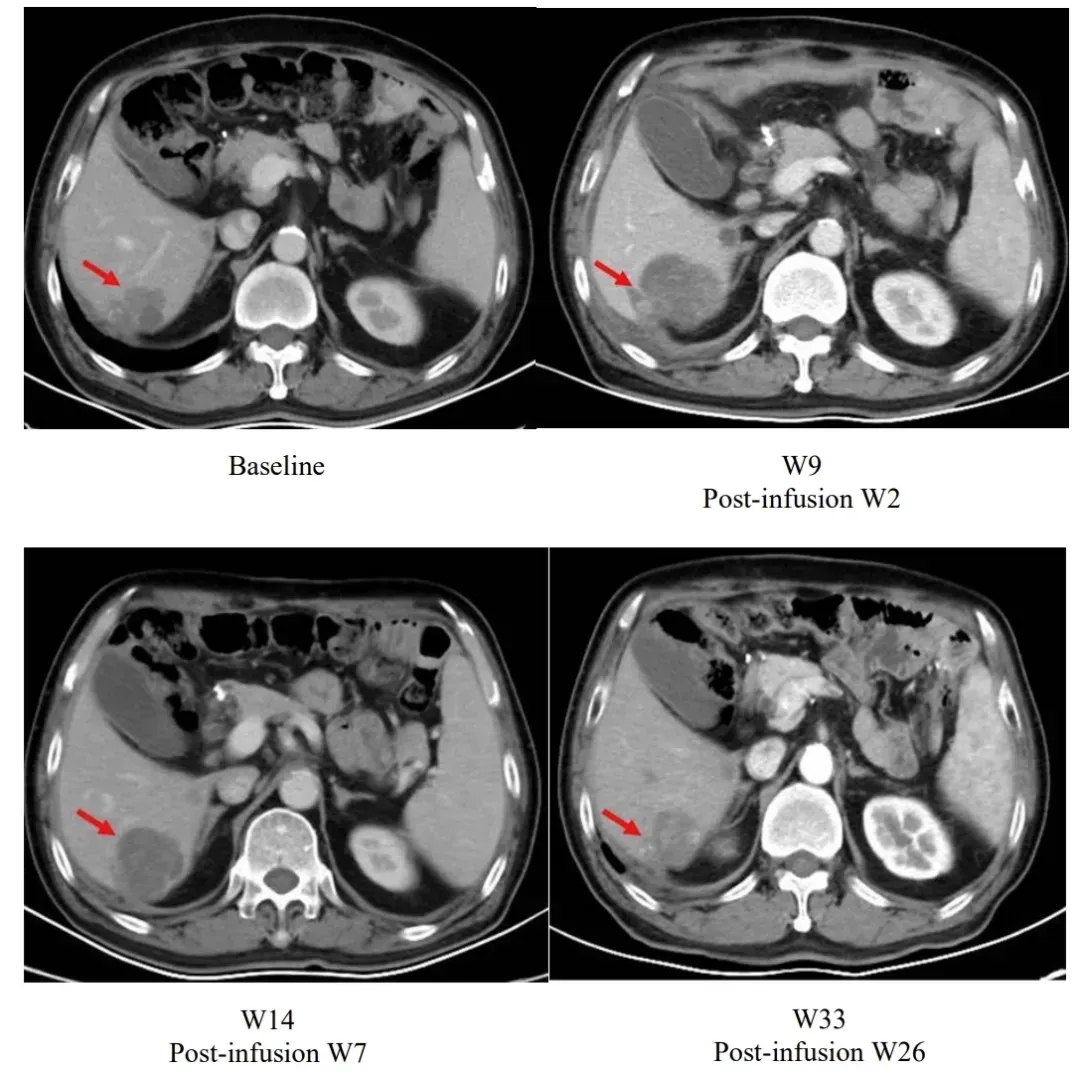

值得一提的是,研究中的一则典型案例展现了独特的治疗响应过程:患者输注satri-cel后第2周肝脏病灶较基线增大,后续持续随访中病灶逐步缩小,至输注后第26周已显著小于基线水平(详见下图)。

▲图源“The Lancet”,版权归原作者所有,如无意中侵犯了知识产权,请联系我们删除